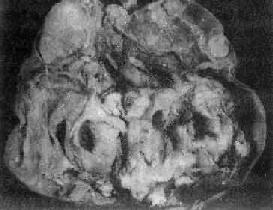

肉眼观,肿多为单侧性,以右侧为多,一般体积较大,平均直径为15~25cm,圆或卵圆形,表面光滑。切面多为实性,质较脆,灰白或粉白色,常有出血坏死及囊性变。镜检,组织形态较复杂及特殊,主要特征有下列几点:①网状结构,是最常见的形态,由星芒状的细胞形成疏松网状结构(图13-23),其中有微型小囊或间隙,囊腔被覆扁平或立方细胞,这种结构类似胚外中胚层结构;②内胚窦样结构,立方或柱状的细胞成单层排列,包绕毛细血管,形成一血管套样结构,这种结构横切面很像肾小球,称为Schiller-Duval小体,这种小体和大鼠胎盘内的Duval内胚窦结构相似,这种结构可能是由卵黄囊衍生演变而来;③多泡性卵黄囊样结构,特征是由扁平上皮、立方或低柱状的细胞形成大小不等的囊腔,其间隔以致密的结缔组织或疏松的粘液样间质,这种结构与胚胎时期的卵黄囊(胚外内胚层)相似;④在细胞内及细胞间隙可见PAS阳性的大小不等的嗜酸性小滴,免疫组化显示这种小滴含有甲胎蛋白(AFP),正常情况下,卵黄囊可合成AFP;⑤可见腺样、乳头状及实体细胞团结构等。

图13-23 内胚窦

呈疏松网状粘液样结构,其中有互相沟通、衬以上皮的腔隙及小囊腔,在细胞内外可见嗜酸性玻璃样小球及基底膜样物